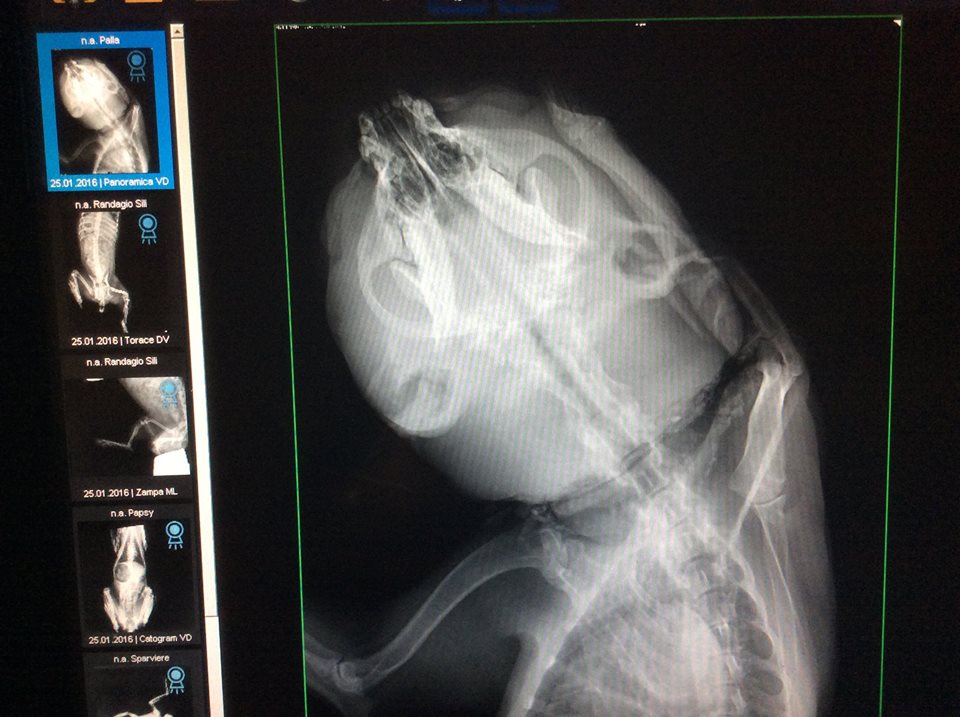

Cagnolina con muso deformatoORISTANO – La Clinica Veterinaria “Duemari” di Oristano ha recuperato ieri una cagnolina che cercava di cibarsi rubando il mangime alle galline. L’animale, la cui provenienza è ancora oscura, ha rischiato di venire decapitato a causa di un laccio di nylon stretto intorno al collo. “Naturalmente non sappiamo come sia successo – ha commentato il responsabile della clinica – Magari le è stato messo un laccio da piccola e poi nella crescita si è stretto. Vista la gravità della ferita stimiamo che sia vecchia di mesi”. La cagnolina ha ora ha la testa molto gonfia e deformata perché il sangue non defluiva correttamente. I medici non sono neppure riusciti a capire di che razza sia, anche se pensano che si tratti di un pitbull.

I veterinari hanno deciso di soprannominare la dolce cagnolina “Palla”. L’animale sta ricevendo le prime cure e sulla pagina Facebook della clinica, dove la sua triste storia è stata resa pubblica, ci sono continui aggiornamenti. Molti sono rimasti indignati dalla cattiveria mostrata nei confronti della cagnolina. “Non ho mai visto niente del genere” ha commentato uno dei veterinari. Tra gli utenti è anche partita una gara di solidarietà per sostenere economicamente le cure di Palla, le cui disavventure sembrano finalmente giunte alla fine.